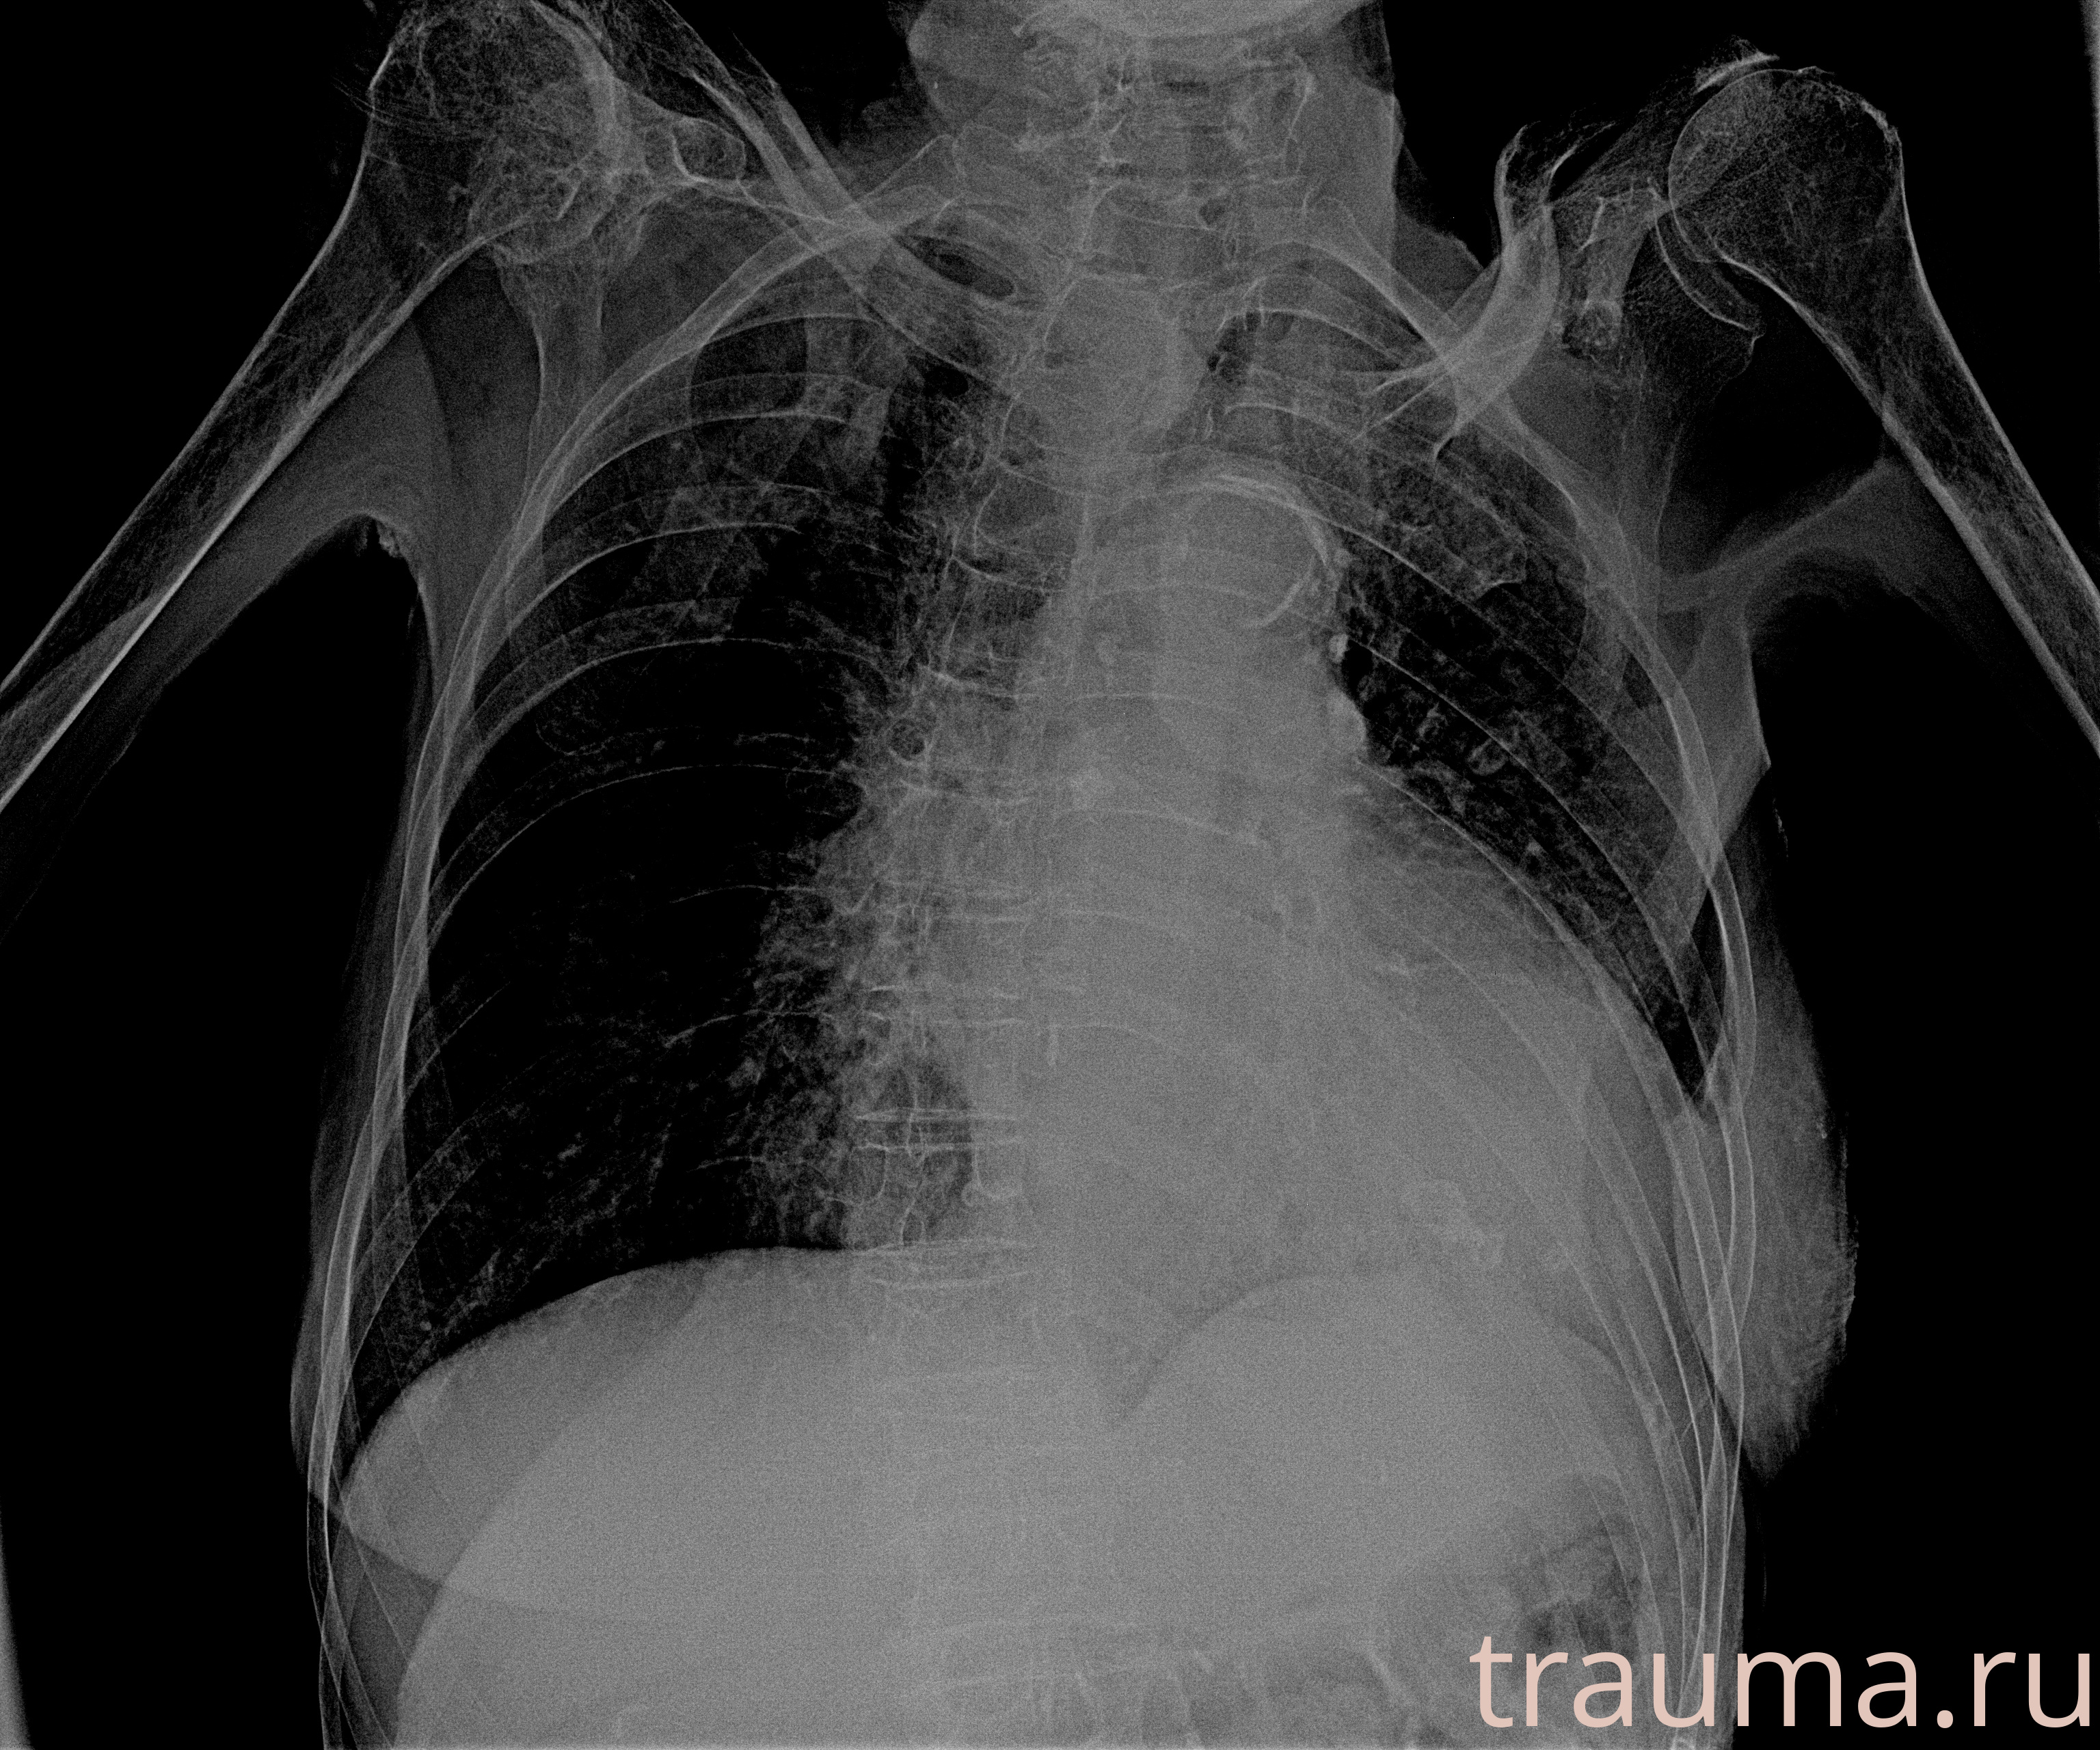

Рентген на дому: по вашему адресу приезжает врач-рентгенолог, травматолог-ортопед с мобильным рентгеновским аппаратом, проводит диагностику травмы или заболевания, делает необходимые рентгенограммы, дает рекомендации по дальнейшему лечению. Получить качественные снимки в домашних условиях возможно благодаря уникальной методике, разработанной МосРентген Центром для института  Склифосовского